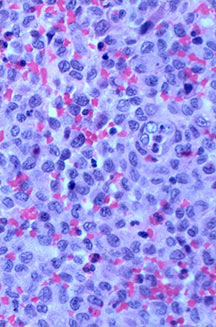

Microscopic Pathology

- Langerhans cell is diagnostic and clonal proliferation

- Nuclei show prominent nuclear groove (coffee-bean)

- Also composed of eosinophils and other inflammatory cells (non diagnostic component)

- Ratio of inflammatory cells to Langerhans cells varies

- Mitotic activity low

- Eosinophils dominate some areas forming diffuse sheets, excluding Langerhans cells

- Birbeck Granules: Electron Microscopy demonstrates granules that often take the form of a tennis raquet and form from complex invaginations of the cell membrane

- Vimentin, CD1 and S-100 positivity